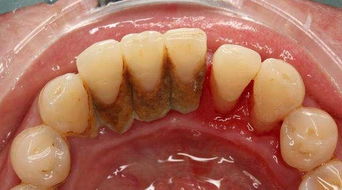

牙科醫(yī)生一般建議每半年洗一次牙結(jié)石,這樣可以減輕牙齦炎、牙周炎的炎癥狀況,但靠單純洗牙是不能治愈牙周病的。要治好牙周病,還應(yīng)該在洗牙之后進行進一步的診斷和口腔專業(yè)的治療。

牙結(jié)石較厚,宜分次潔牙:牙結(jié)石較多較厚、藥物抗炎效果欠佳或脫敏醫(yī)治欠佳者,建議分次潔牙。

定期潔牙:常年累積的牙結(jié)石又多又硬,致使?jié)嵮罆r需加大潔牙機的強度才能去除,這樣會加重牙齒酸痛感。因此建議大家定期到醫(yī)院潔牙,剛構(gòu)成的牙結(jié)石量不多,質(zhì)較松,易去除,不易形成潔牙時的酸痛感。